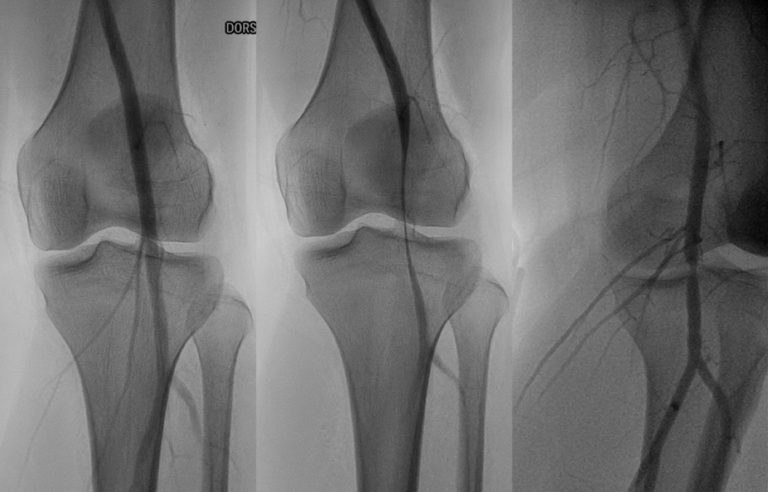

Genicular artery embolization is a minimally invasive procedure that targets the genicular arteries, which are …